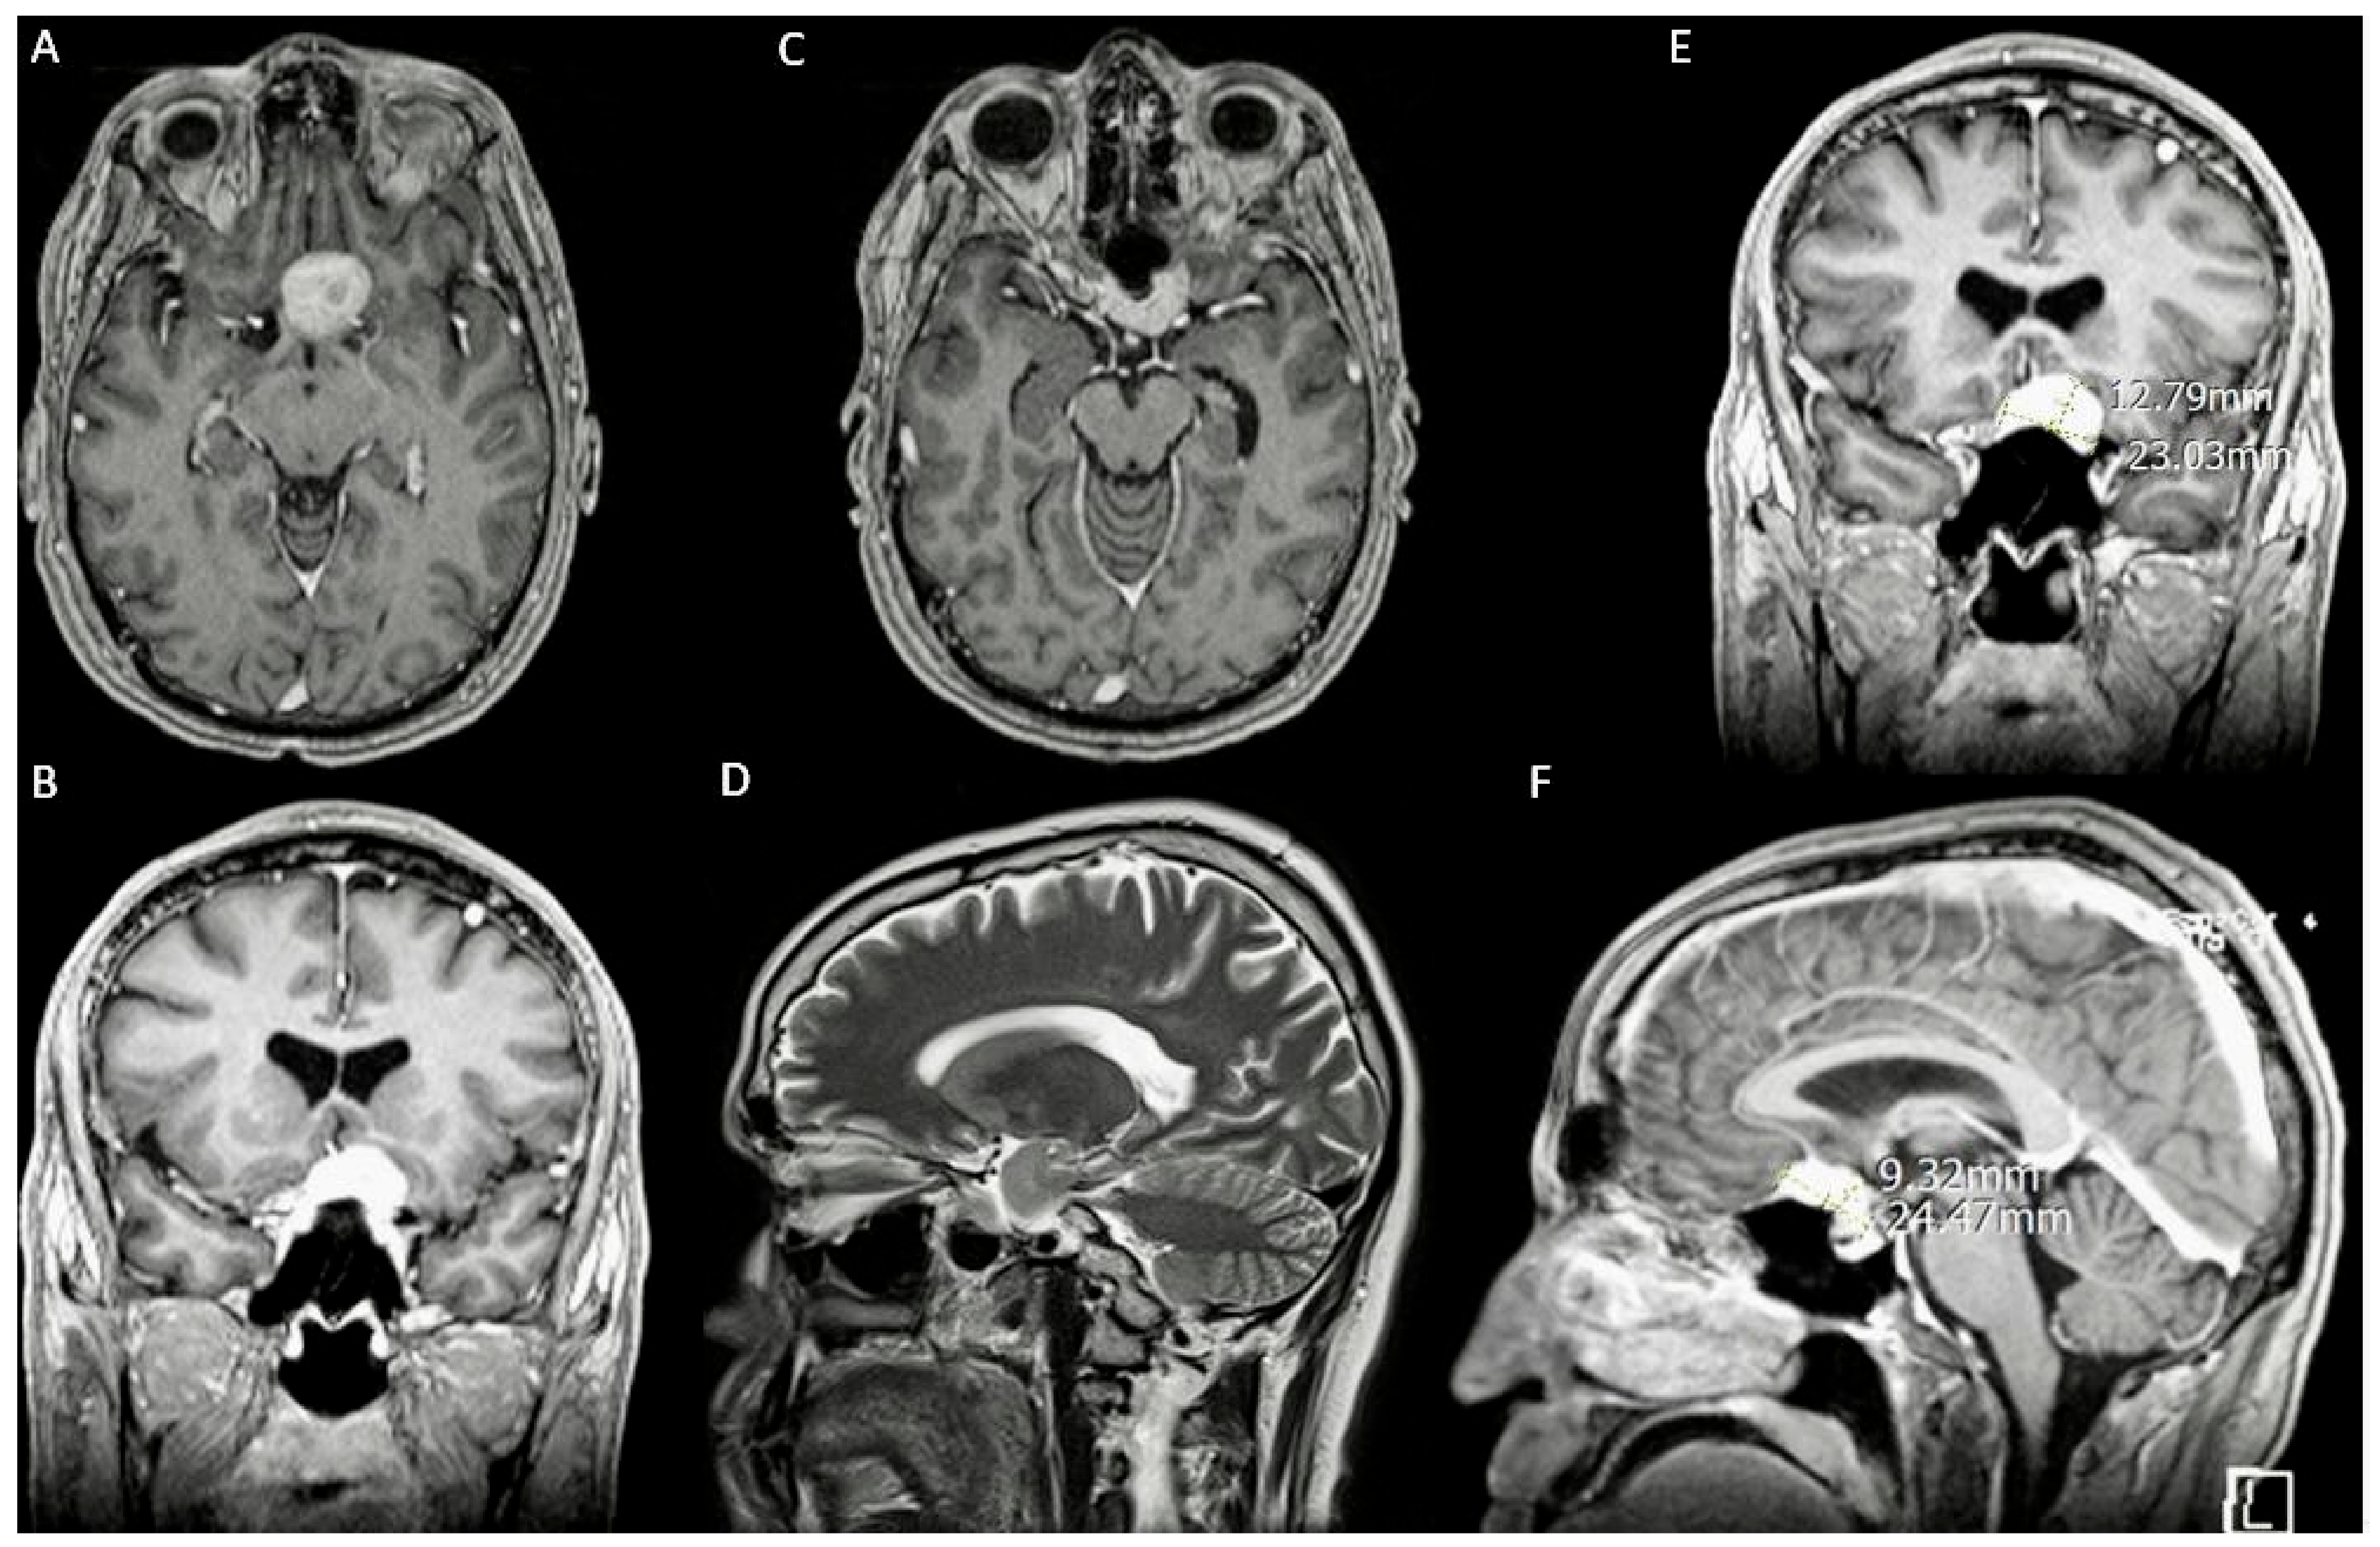

3.1. Case 1

3.1.1. Demography, Presentation, and Evaluation

3.2. Case 2

3.2.1. Demography, Presentation, and Evaluation